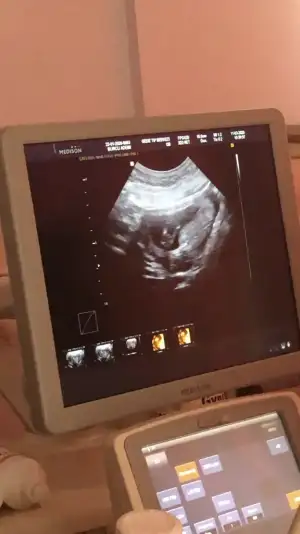

İlk iki foto alttan bakılandan son foto normal daha öncede atmıstım ama cok belli değil demiştiniz bu şekilde bi tahmin olabilirmi Ikra meyra Ikra meyra ☺️